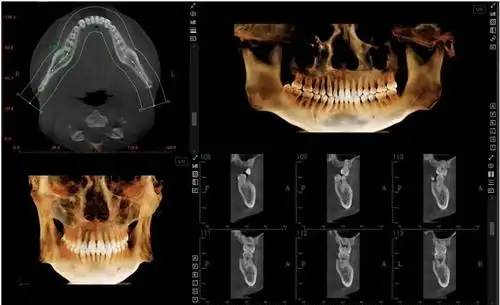

牙医520重磅发布这台有ai的口腔cbct来了